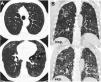

Expiratory CT scan is a complementary technique of inspiratory CT that provide valuable physiological information and may be more sensitive to detect air trapping than pul-monary function tests. It is useful in many obstructive airway diseases, including obliterative bronchiolitis, asthma, Swyer-James syndrome, tracheomalacia, hypersensitivity pneumonitis and sarcoidosis. In obliterative bronchiolitis, expiratory CT scan may be the only imaging technique that shows abnormalities in the early phase of disease. In order to obtain a good quality study, we should explain the procedure to the patient, use precise instructions and do some practice before image acquisition. Here we describe strategies to optimize the techni-que and propose an algorithm that help in interpretation of imaging findings in patients with obstructive airway disease.